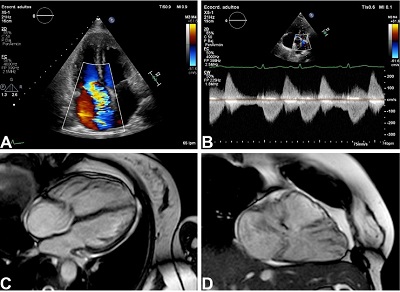

After management with diuretics and improvement of the fluid overload, the patient underwent transthoracic echocardiography showing typical findings of Hedinger syndrome. Cardiac magnetic resonance imaging (MRI) showed a severely dilated right ventricle, torrential tricuspid regurgitation, and severe pulmonary regurgitation (Figure 1). Her levels of 5-hydroxyindoleacetic acid demonstrated good medical treatment. Given these findings, surgical replacement of the tricuspid and pulmonary valves was decided by the Heart Team.

Typical findings of Hedinger syndrome include severe right-sided valve dysfunction with right ventricular dilation/dysfunction. The tricuspid and pulmonary valves have thickened leaflets that severely impair their motion and coaptation, causing severe regurgitation and right ventricular systolic dysfunction. Although transthoracic echocardiography can accurately assess tricuspid regurgitation, cardiac MRI may be required for evaluation of right ventricular systolic function, especially in cases with pulmonary valve dysfunction. Left-sided valve dysfunction is extremely rare (the pulmonary vascular bed usually metabolizes the released substances), and whenever present should always raise suspicion of pulmonary metastases[3].